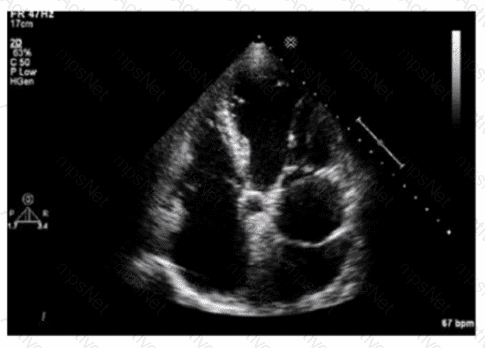

What is the incidental finding seen by color Doppler in this four-chamber view of a patient with left atrial enlargement?